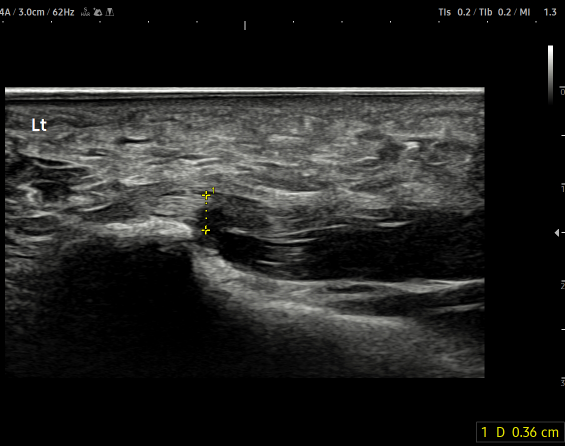

- 치료기간 : 25 .6 .19 ~ 25 . 10 . 23

- 치료횟수 : 15 회 (아피톡신+극초단파)

치료 전 (족저근막 두께 0.44~0.61cm)

치료 후 (족저근막 두께 0.33~0.36cm)